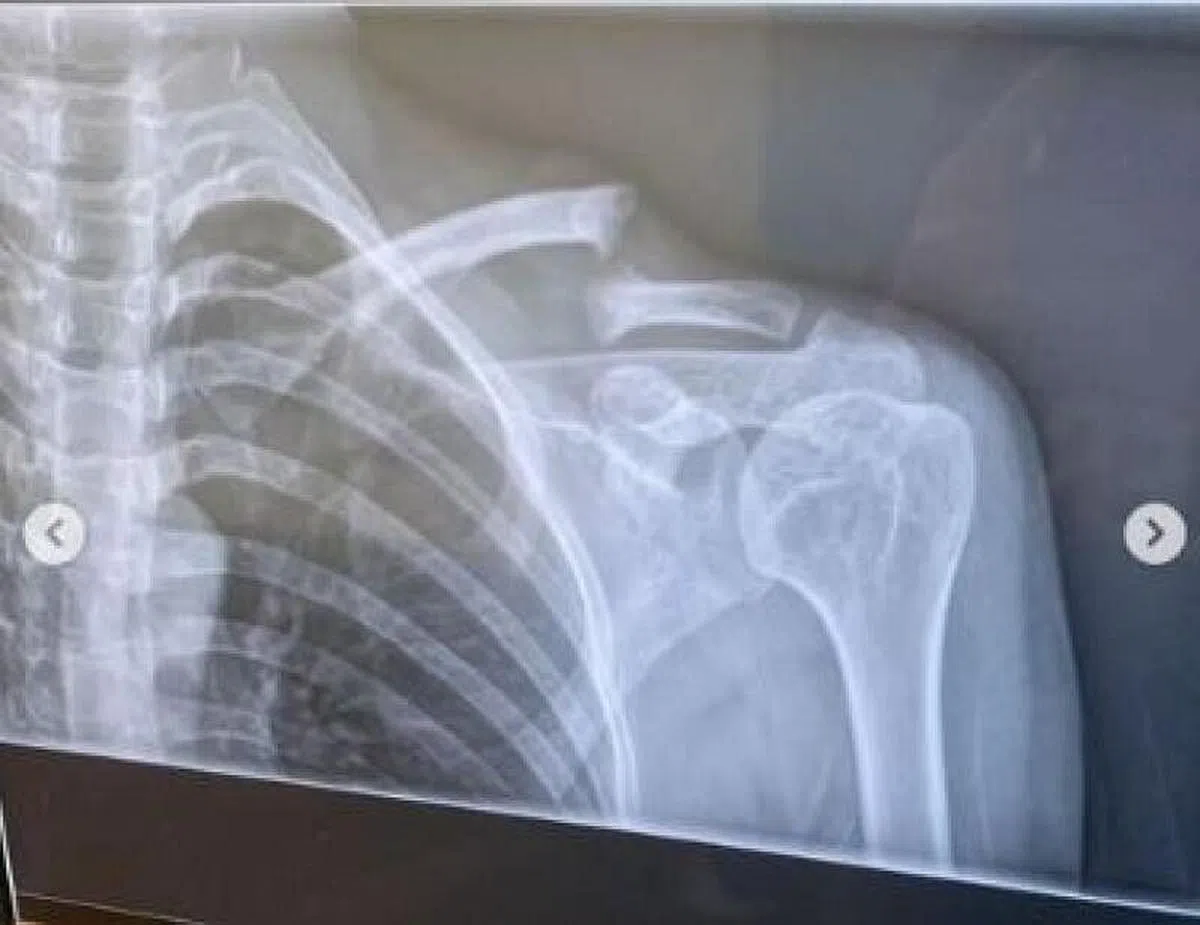

赵彩聆昨晚(3月25日)在IG晒出两张照片,一是坐着轮椅,另一是X光照片,透露她骑脚踏车发生意外,伤及锁骨,需要动手术。

赵彩聆说,意外发生后,她被送往医院检查,医生证实她的锁骨骨折,下星期需要进行骨骼组织移植(bone graft)手术。也因为如此,她被迫取消手头上的工作。